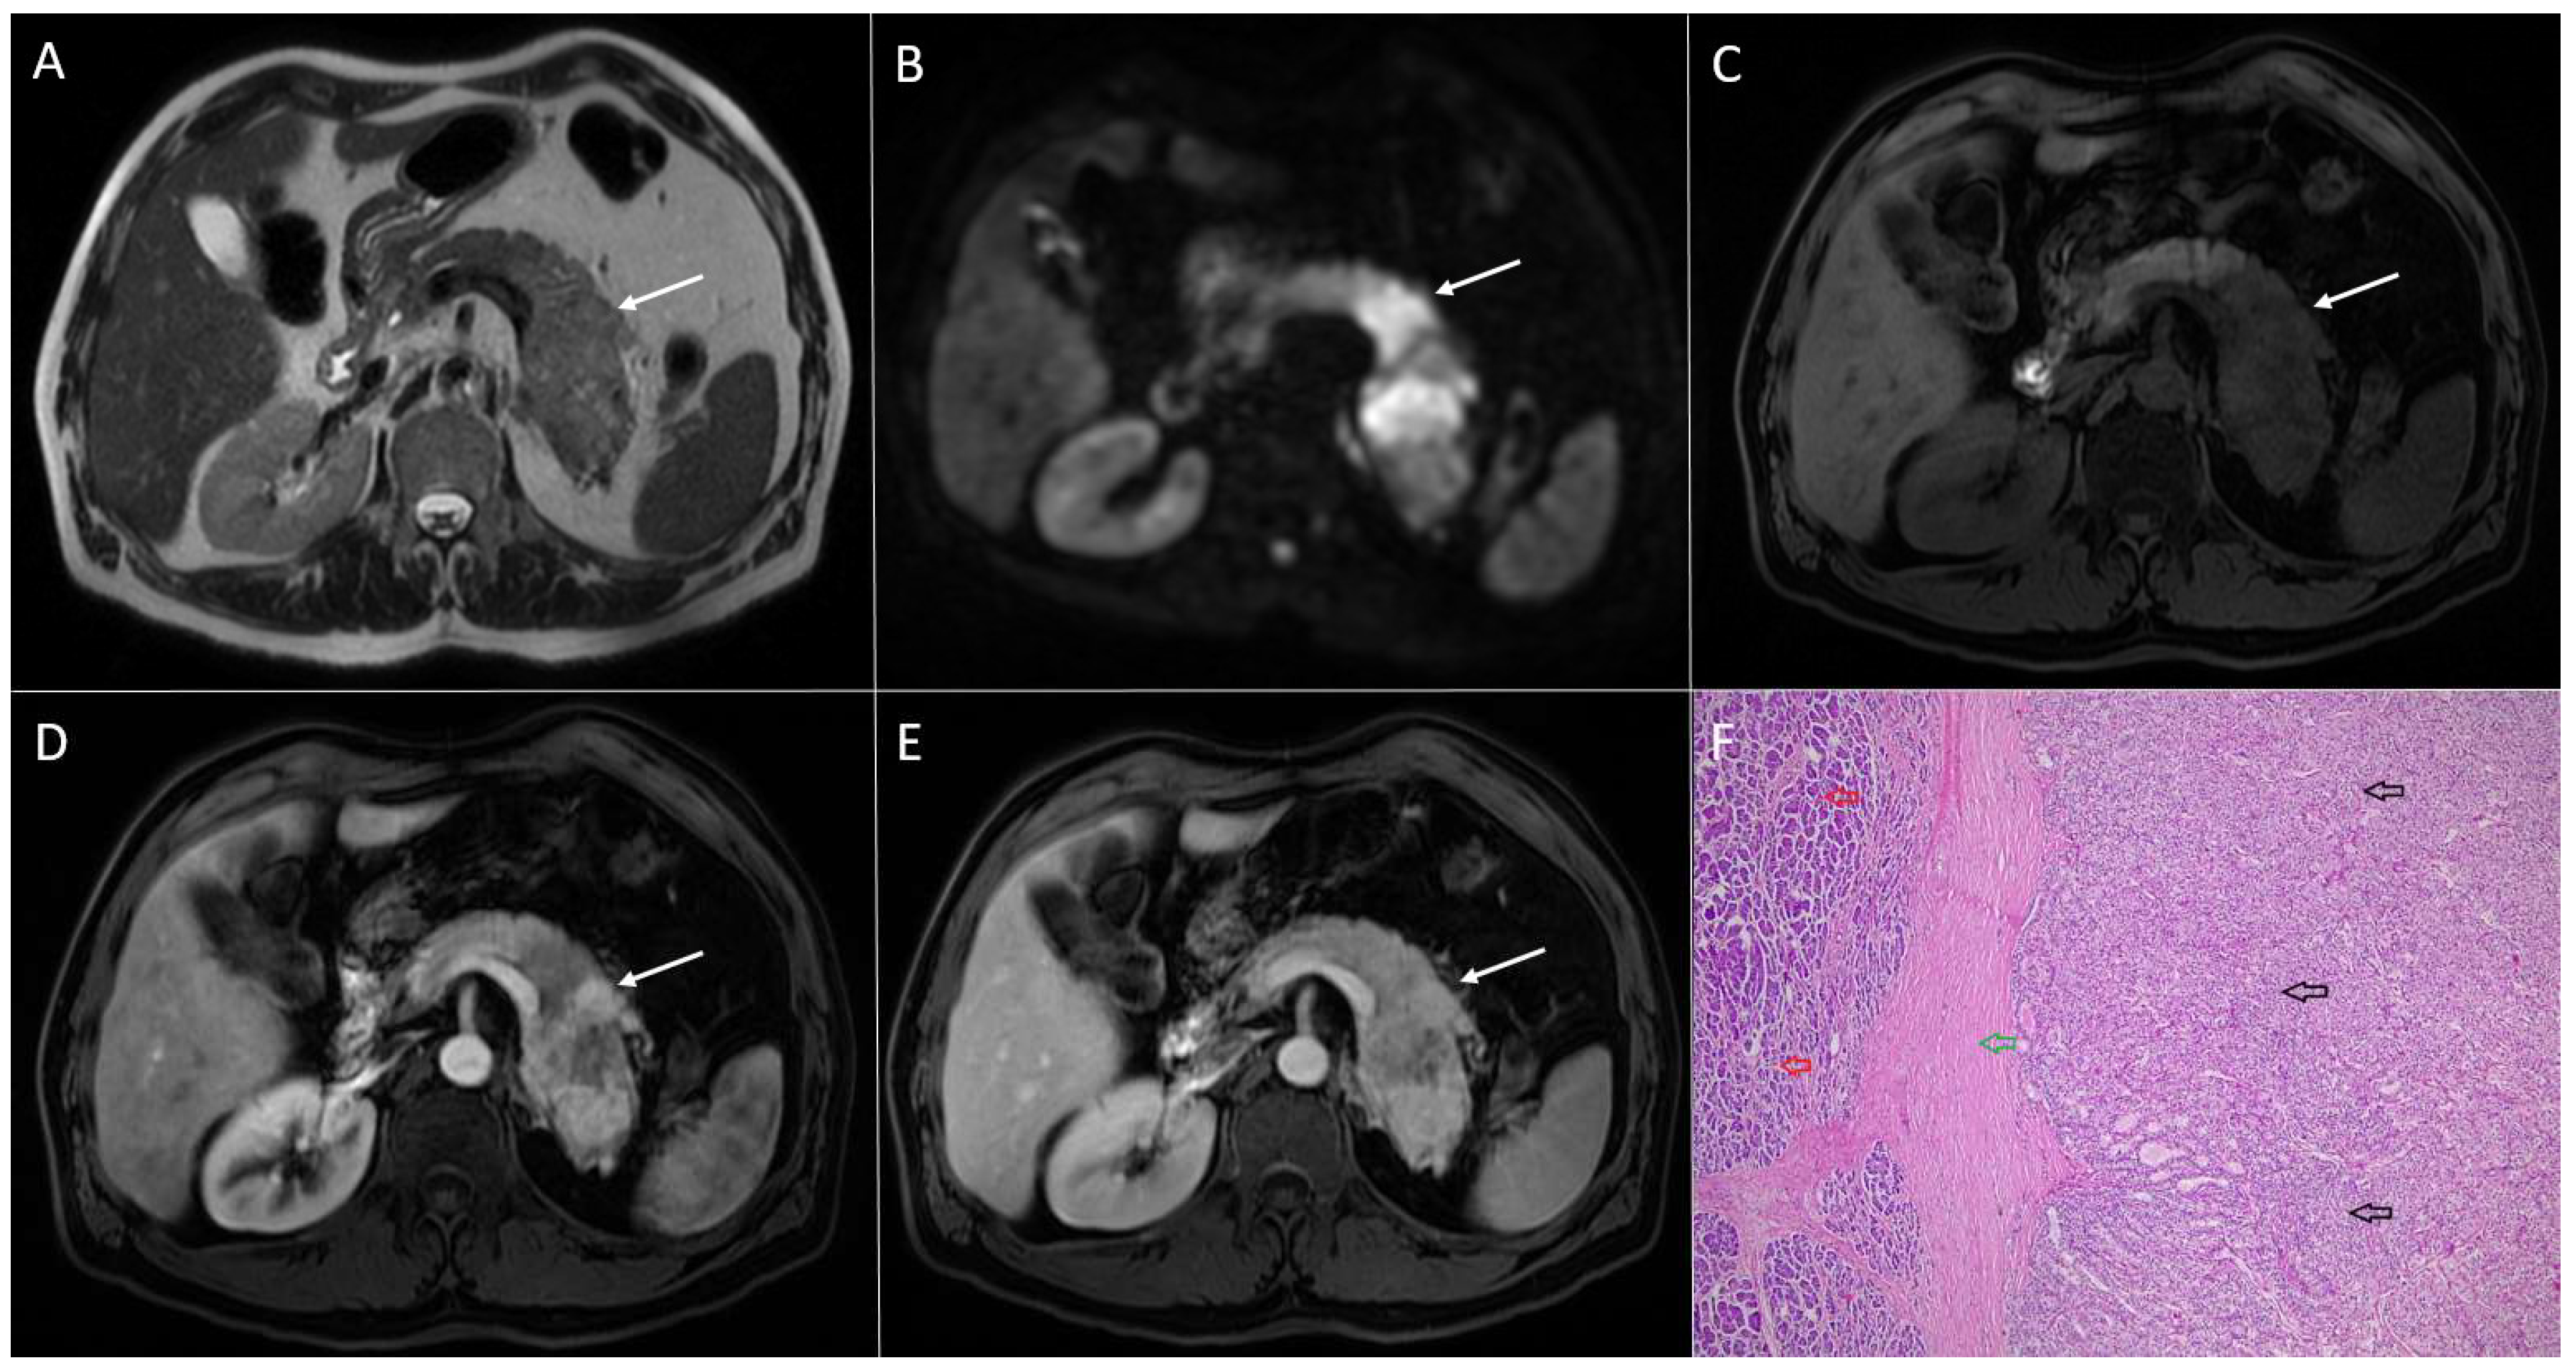

2. Typical Imaging Presentation of Solid Pseudopapillary Neoplasms